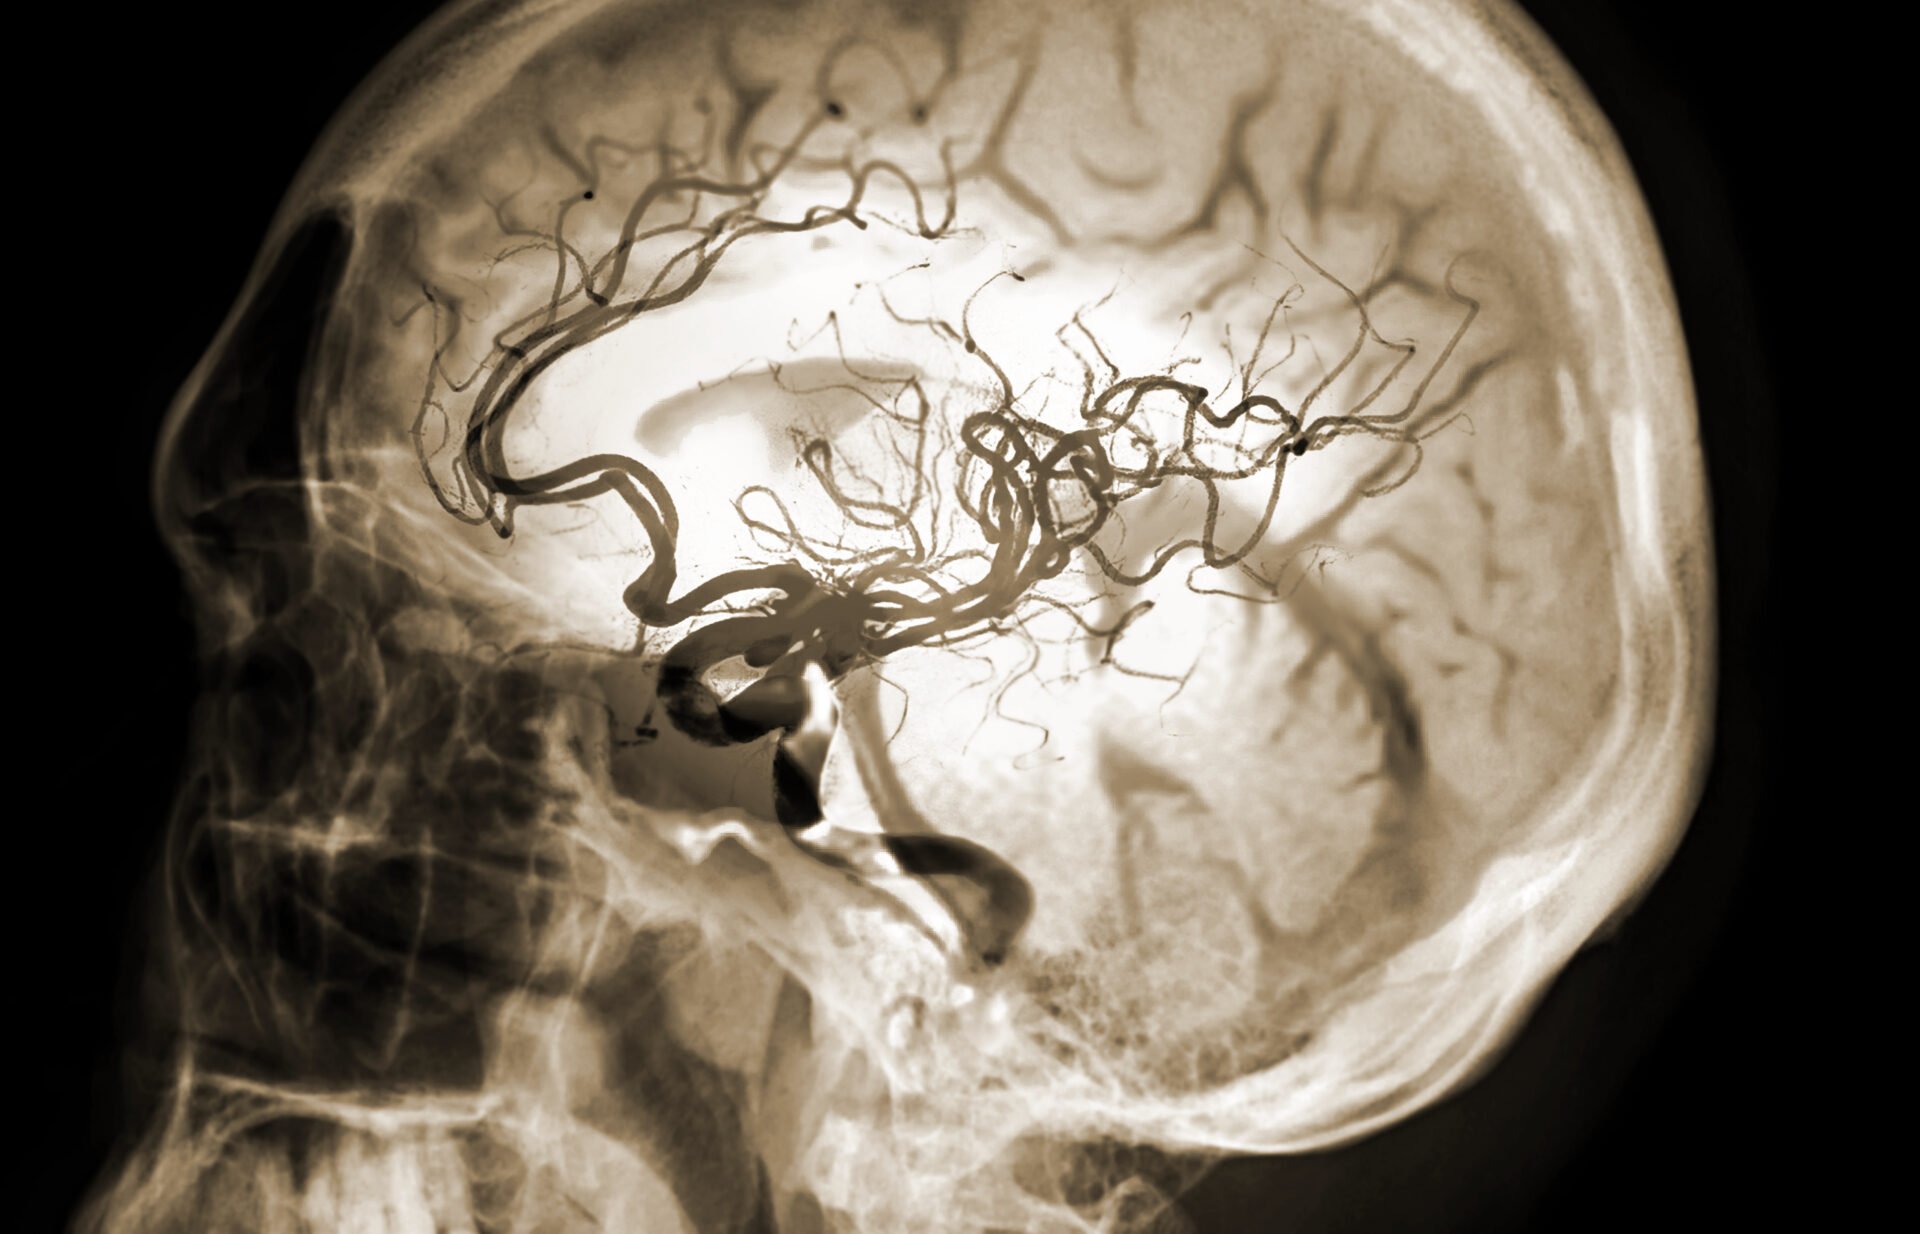

In essence, the purpose of a stroke public health campaign is to save lives by seeking to change people’s behaviour when a stroke is suspected. Stroke is a medical emergency and requires rapid medical attention; therefore, any stroke public health campaign must prioritise seeking emergency medical treatment quickly.

Due to this requirement of quick treatment, a stroke public health campaign must also seek to educate the public about stroke symptoms. If a stroke cannot be identified early due to a lack of knowledge within the general population, then emergency medical attention will not be sought, with potentially devastating consequences. It is also important to note that stroke can happen to everyone (and anyone could be asked to respond to somebody else having a stroke), meaning that the stroke public health campaign must be aimed at everyone in the general population.